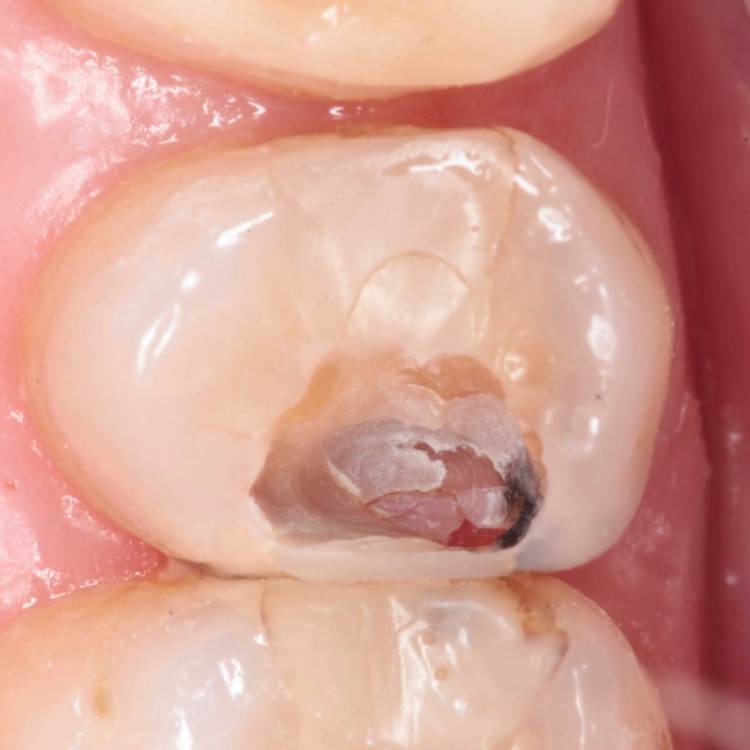

Гарриевич Опубликовано 3 мая, 2022 Автор Поделиться Опубликовано 3 мая, 2022 (изменено) Гемостаз и перекрытие мта гуттой Изменено 3 мая, 2022 пользователем Гарриевич 1 Ссылка на комментарий

Kolchanov Опубликовано 8 мая, 2022 Поделиться Опубликовано 8 мая, 2022 08.05.2022 в 00:55, Гарриевич сказал: Костя, а что тебе до картинки? А первые два пункта ты что пропустил? Я еще на канале у Рикуччи хотел поинтересоваться, в чём смысл, когда он бором в канале пульпу иссекает вместе со стенками. Но, потом увидел в комментах, что он отвечает в стиле я сам сусам и не стал вопрошать. В представленном случае, я вижу классический эндодоступ и расширение устья не меньше, чем при эндо. Натурально, тут, что делать пульпотомию, что пульпэктомию, по времени одно и то же. Поэтому даже на лень не списать. Остаётся только упомянутое "ради интереса". Ссылка на комментарий

Гарриевич Опубликовано 9 мая, 2022 Автор Поделиться Опубликовано 9 мая, 2022 7 часов назад, Korabahtoff сказал: Гутта из инжектора не обжигает пульпу? Гутта из инжектора идёт поверх мта, то есть не контактирует с пульпой Ссылка на комментарий